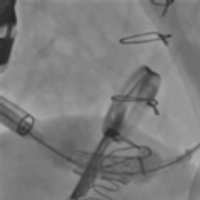

病例四(经颈静脉三尖瓣瓣中瓣)

患者女性,69岁,既往行三尖瓣生物瓣置换术,置入HANCOCK II 29#瓣膜一枚。STS评分11.75%,属于外科换瓣手术高风险患者。术前心脏超声示原三尖瓣生物瓣衰败,瓣叶脱垂,三尖瓣轻度狭窄并中量反流。术前详尽评估,经股静脉路入同轴性不理想,故术中选择经右颈静脉途径植入27# Renato球扩式瓣中瓣,释放成功后瓣膜功能良好,无明显瓣中及瓣周反流,平均跨瓣压差2.8mmHg。

瓣膜释放 术后右室造影